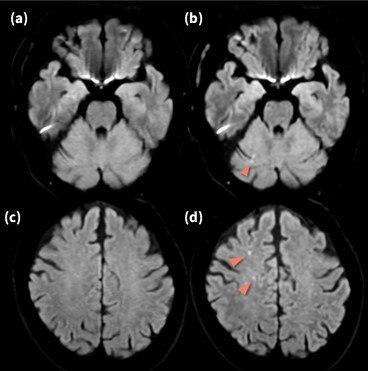

専用 脳MRI 3 高性能MRI(1.5テスラ)|施設・設備|おおたけ脳神経・漢方内科の詳細情報

高性能MRI(1.5テスラ)|施設・設備|おおたけ脳神経・漢方内科。今回導入された3T-MRIについて|名古屋セントラル病院。1.5T MAGNETOM ESSENZA 頭頸部領域における質の高い診断と検査。